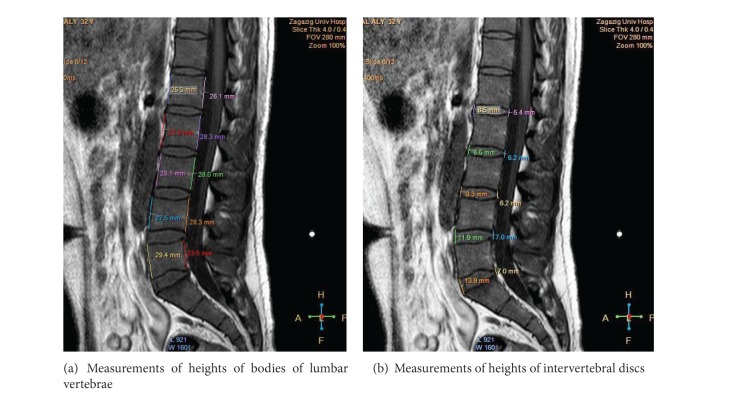

尽管人们越来越认识到腰椎前凸的功能和临床重要性,但对其描述知之甚少,特别是在埃及。与此同时,磁共振成像(MRI)作为一种无创诊断技术已被引入。本研究的目的是利用正中矢状位核磁共振检查腰椎前凸的解剖结构。93例正常腰椎mri(男性46例,女性47例;25-57岁)进行回顾性评价。腰椎曲度及其节段“椎骨和椎间盘”被描述和测量。女性腰椎前凸角(LLA)大于男性。其平均值随年龄增长而增加。男性腰高(LH)高于女性。同时,女性腰宽(LB)高于男性。腰椎指数(LI = LB/LH × 100)性别差异有统计学意义(P < 0.0001)。腰椎前凸是由下腰椎的椎间盘和椎体楔入形成的。总之,MRI可以清楚地显示腰椎前凸的解剖结构。结合LLA使用LI可用于评估腰椎前凸。

Despite the increasing recognition of the functional and clinical importance of lumbar lordosis, little is known about its description, particularly in Egypt. At the same time, magnetic resonance imaging (MRI) has been introduced as a noninvasive diagnostic technique. The aim of this study was to investigate the anatomy of the lumbar lordosis using midsagittal MRIs. Normal lumbar spine MRIs obtained from 93 individuals (46 males, 47 females; 25-57 years old) were evaluated retrospectively. The lumbar spine curvature and its segments "vertebrae and discs" were described and measured. The lumbar lordosis angle (LLA) was larger in females than in males. Its mean values increased by age. The lumbar height (LH) was longer in males than in females. At the same time, the lumbar breadth (LB) was higher in females than in males. Lumbar index (LI = LB/LH × 100) showed significant gender differences (P < 0.0001). Lordosis was formed by wedging of intervertebral discs and bodies of lower lumbar vertebrae. In conclusion, MRI might clearly reveal the anatomy of the lumbar lordosis. Use of LI in association with LLA could be useful in evaluation of lumbar lordosis.